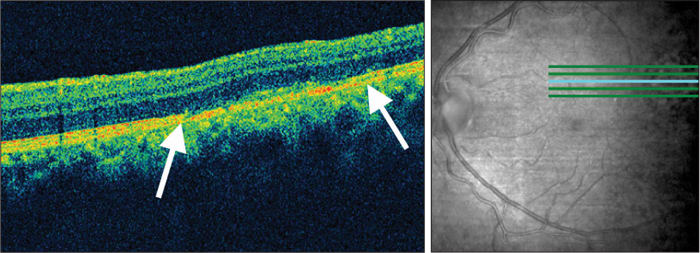

An oval, one-disc–diameter area of retinal atrophy and retinal pigment epithelium (RPE) attenuation was noted in the left eye superotemporally to the macula but without involvement of the fovea (Figure 1). Fluorescein angiography showed a well-circumscribed mottled hyperfluorescent pattern, consistent with phototoxic retinopathy (Figure 2). Spectral-domain optical coherence tomography (SD-OCT) scans of the lesion showed loss of the inner segment/outer segment junction with disruption of the underlying RPE (Figure 3). Central macular thickness was within normal limits, without photoreceptor disruption or edema. The fundus had been normal on preoperative examination. The patient had no history of diabetes or other systemic health problems and took no medications. The fellow eye's fundus was unremarkable other than a posterior vitreous detachment.

Figure 3. Spectral-domain OCT horizontal scan of light-induced retinopathy, showing loss of inner segment/outer segment junction with disruption of the underlying retinal pigment epithelium (arrows).

The patient's fundus appearance and fluorescein angiography were typical of those previously described as phototoxicity as caused by the light of operating microscopes.1-4 Optical coherence tomography findings in solar retinopathy were reported by Bechmann and associates using a first-generation OCT scanner.5 They described the main finding as a hyper-reflective area involving all retinal layers in two patients after watching a solar eclipse. In this patient, evaluation using a spectral-domain OCT demonstrated full-thickness fragmentation of photoreceptors and RPE.